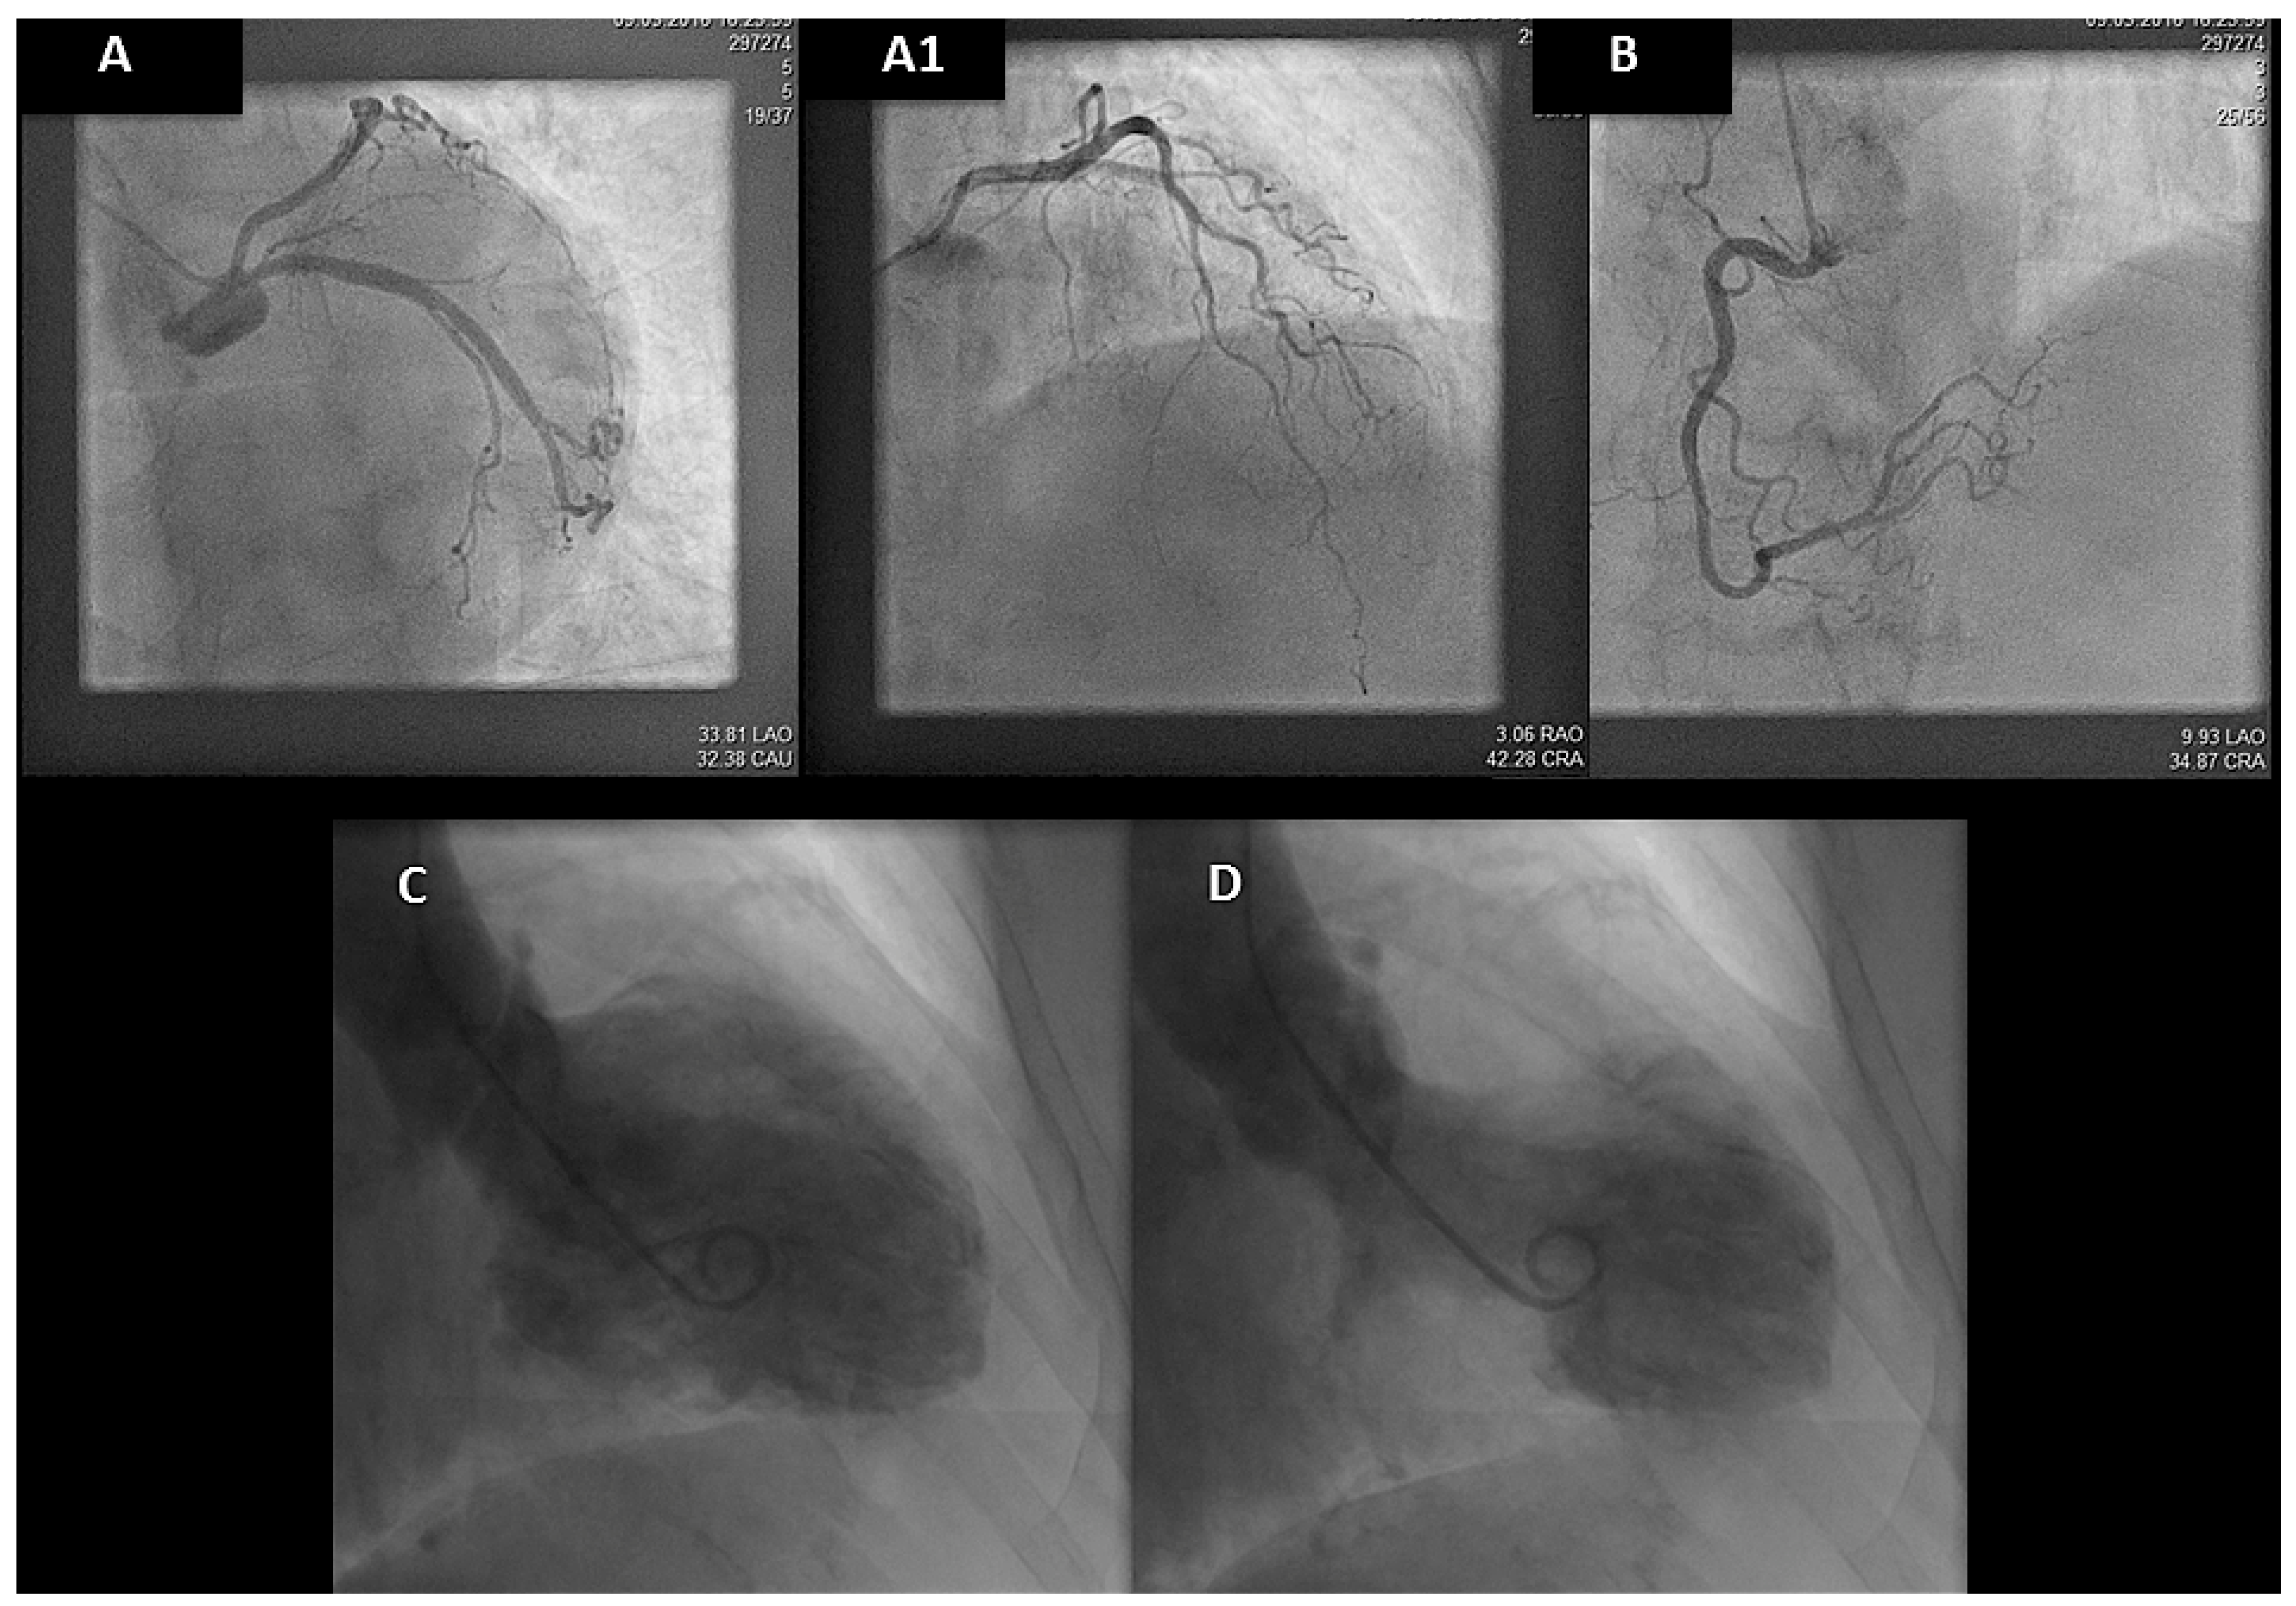

TTE revealed extensive left ventricular apical akinesia with moderate systolic dysfunction. High-sensitive troponin I was elevated (797 ng/l; reference range <40 ng/l). Urgent coronary angiography showed normal coronary arteries (Figure 4, panel A, A1 and B), and ventriculography revealed apical ballooning (Figure 4, panel C and D).

Figure 4.

Coronary angiography. Panel A-A1-B showed normal coronary arteries; panel C-D venticulography with apical ballooning.